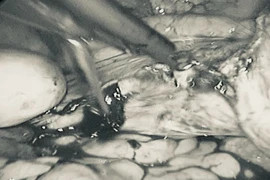

Ngày 07/10, người bệnh được thực hiện mổ tại khoa Ngoại Lồng ngực - Bệnh viện K. Vì là trường hợp u phát hiện sớm, các bác sĩ đã chỉ định tiến hành phẫu thuật nội soi, cắt thùy trên kết hợp vét hạch.

Phẫu thuật này sẽ cắt bỏ hoàn toàn khối u và hạch di căn, giảm đáng kể nguy cơ tái phát cho người bệnh. Ngoài ra, việc thực hiện với một vết mổ nhỏ, hạn chế gây mất máu cũng giúp người bệnh ít đau đớn, rút ngắn thời gian phục hồi, giảm nguy cơ biến chứng sau phẫu thuật, đặc biệt ý nghĩa với những bệnh nhân cao tuổi như ông H.

Ca phẫu thuật kéo dài gần 3 tiếng và đã thành công loại bỏ được khối u của người bệnh. Sau phẫu thuật 1 ngày, ông H. đã có thể ăn uống trở lại và sau 3 ngày thì hoàn toàn có thể tự vận động, đi lại, đứng ngồi bình thường. Ở độ tuổi của ông H., phục hồi sớm sau phẫu thuật là điều rất đáng mừng.